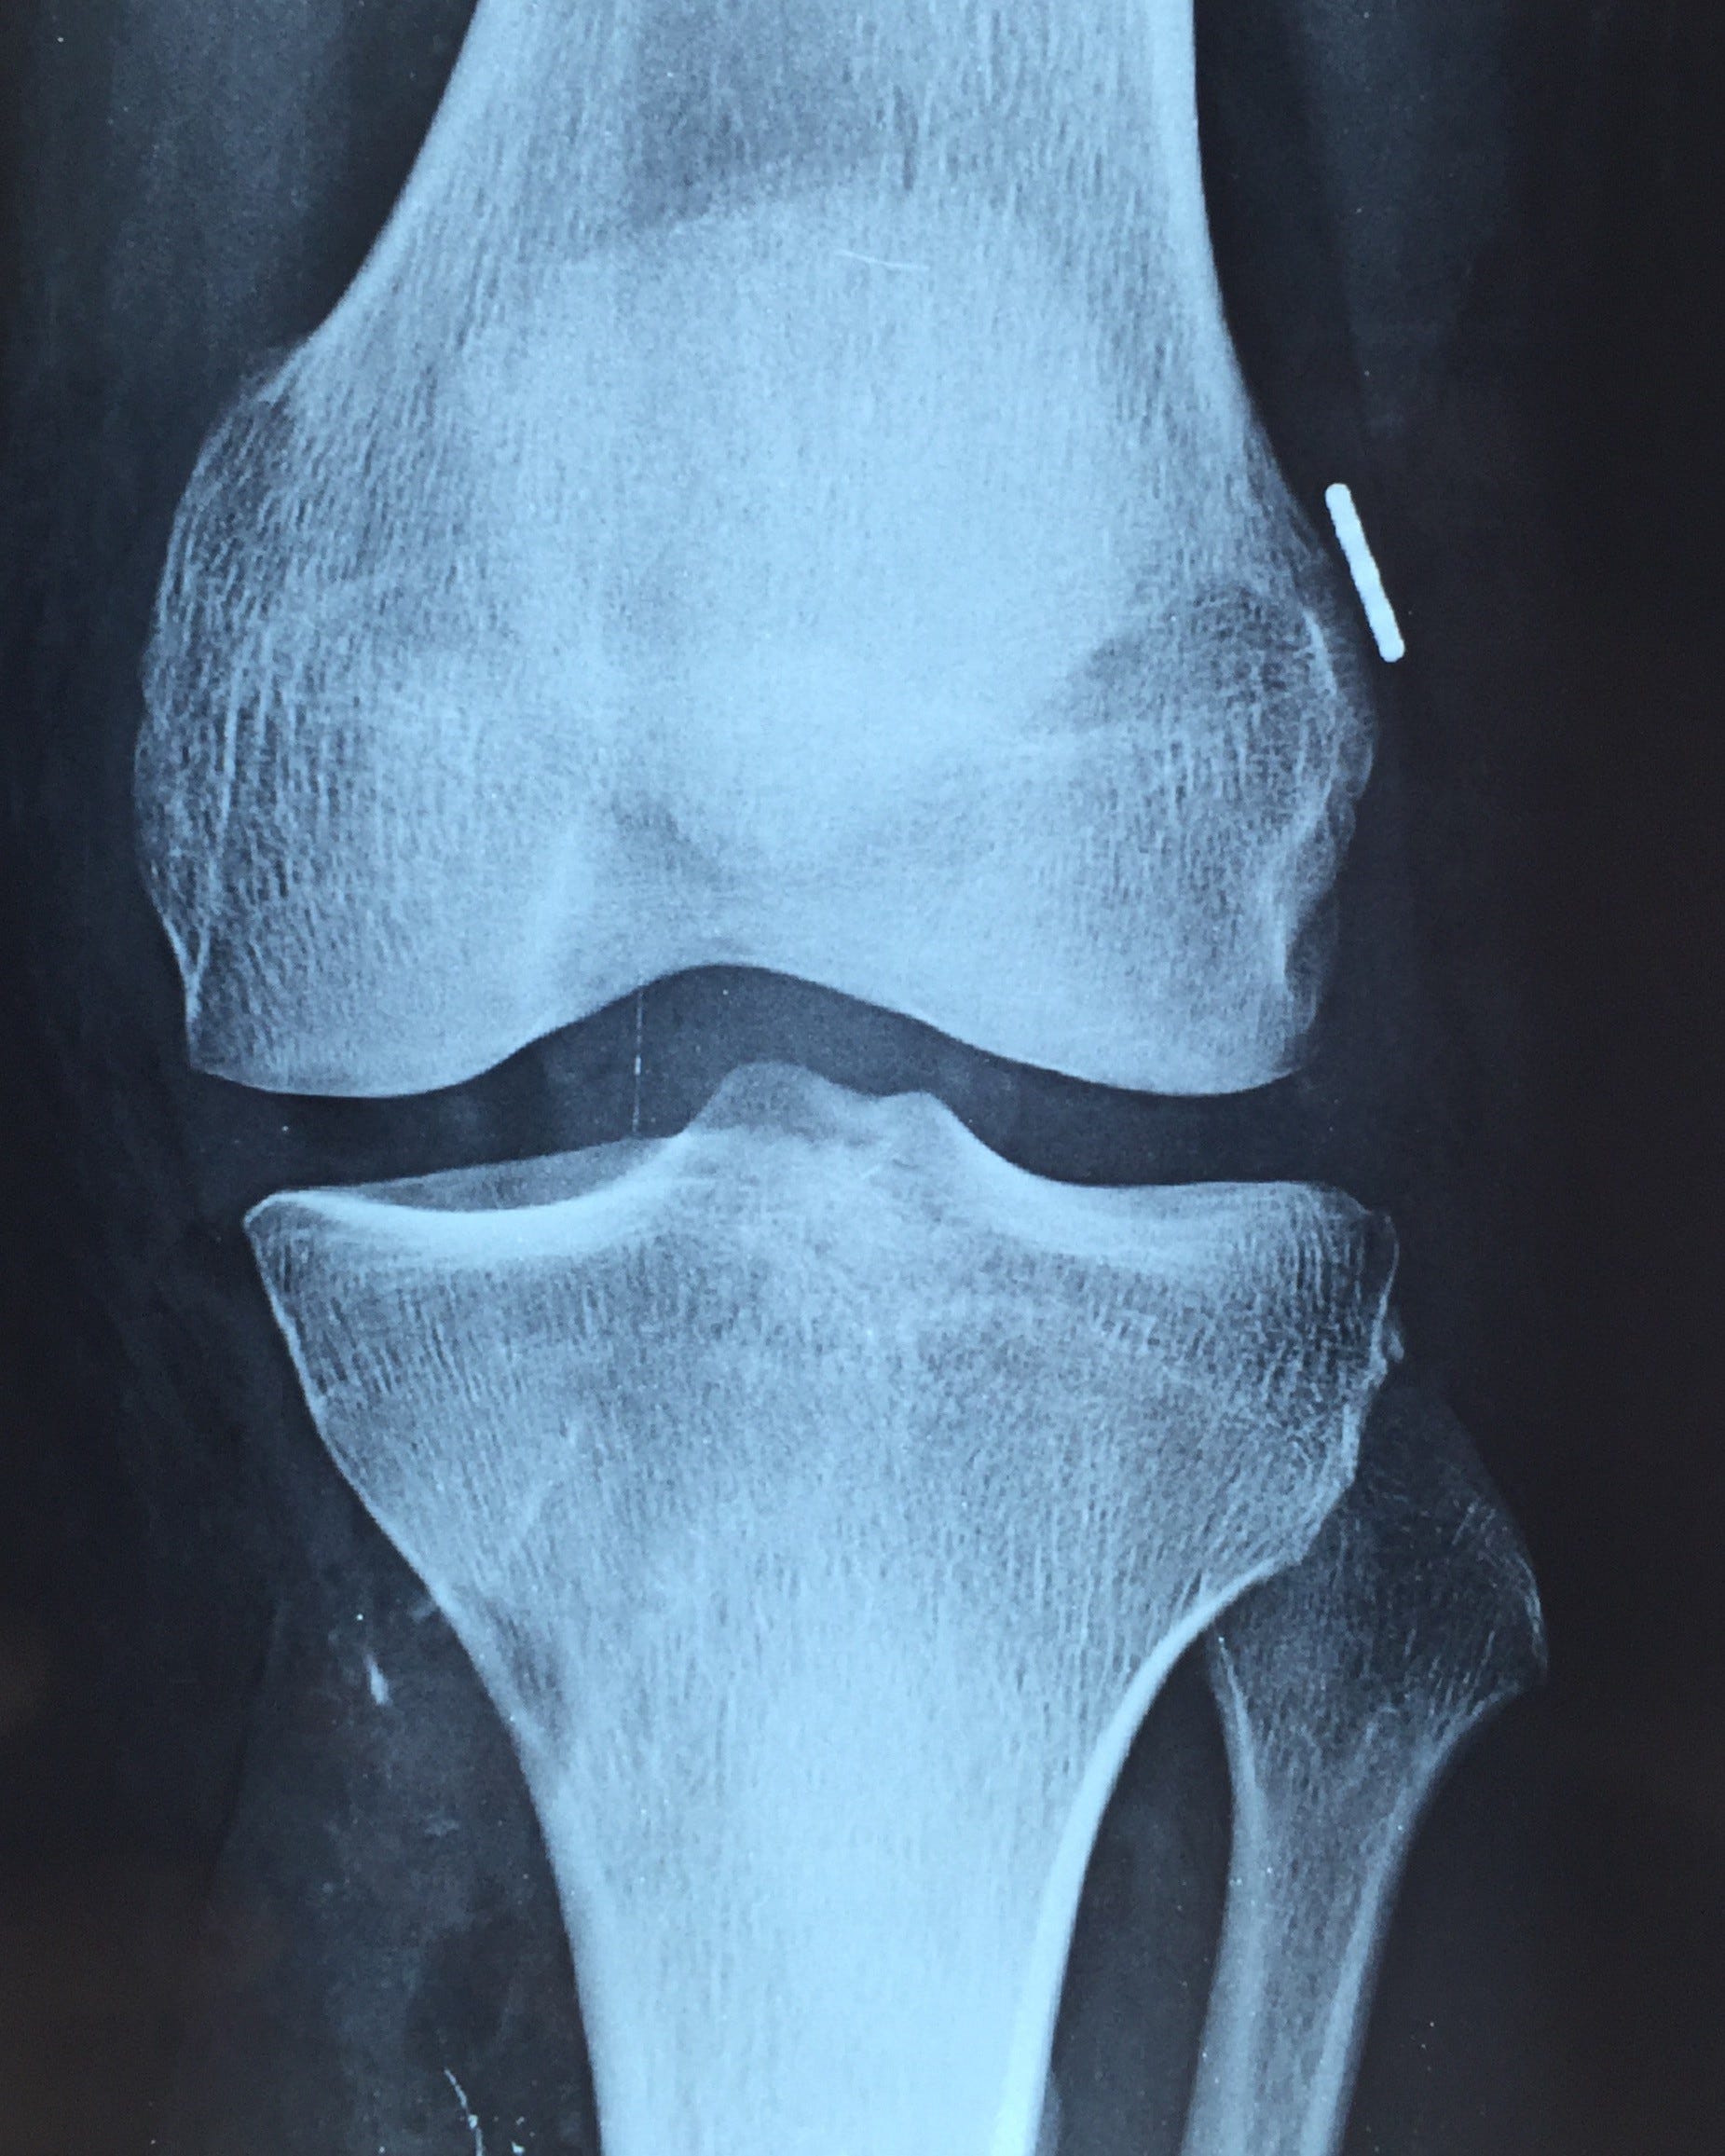

Femoral endobutton and tibial interference screw in keeping with prior acl reconstruction. Anterior cruciate ligament damage is a very common injury especially among athletes.

Normal appearance of a post acl reconstruction knee.